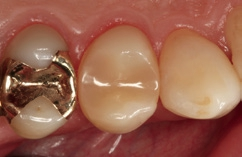

Bei dem 57-jährigen Patienten imponierte in der Routine-Bissflügelaufnahme eine Sekundärkaries an dem mit einem Gold-inlay versorgten Zahn 14 (Abb. 1). Der vitale und symptomfreie Zahn zeigte lediglich radiologisch (Abb. 2) einen Randdefekt distal sowie den Verdacht auf Karies unter dem Befestigungs- bzw. Unterfüllungszement. Nach Entfernung des Goldinlays ergab sich der Verdacht auf eine Pulpaeröffnung (Abb. 3). Klinisch war keine Blutung feststellbar, was allerdings durch die Lokalanästhesie kaschiert sein konnte. Aufgrund der Symptomlosigkeit des Zahnes und fehlender Anzeichen einer Pulpitis (fehlende Blutung) sowie einer Nekrose (erhaltene Vitalität) fiel die Entscheidung zugunsten einer Vitalerhaltung unter Beibehaltung eines engmaschigen Recalls mit Vitalitätsproben. Die Überkappung der Eröffnungsstellen erfolgte als Alternative zu Calciumhydroxid [8] mit einem Portlandzement enthaltenden Flowkomposit mit hohem pH-Wert [7,51] (TheraCal LC, Bisco, Abb. 4). Obwohl dieses Produkt hinsichtlich seiner Effektivität und Zelltoxizität nicht an ProRoot MTA (Dentsply Sirona) und Biodentine (Septodont) [42] herankommt [5,11], ist es hinsichtlich seiner Praktikabilität und der Möglichkeit des sofortigen, zügigen Weiterarbeitens konkurrenzlos. Ein vergleichbares Produkt gibt es z.B. bei Ultradent (Ultra- Blend Plus).